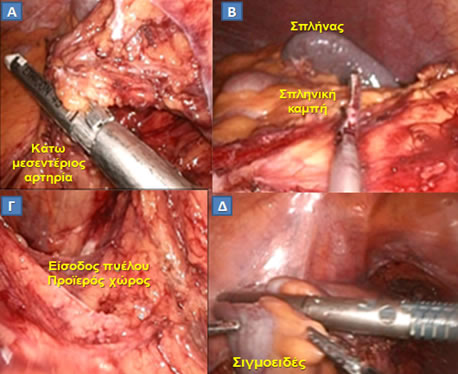

Σύγχρονες προοπτικές τυχαιοποιημένες πολυκεντρικές μελέτες έχουν αποδείξει ότι, εφόσον υπάρχει η κατάλληλη εμπειρία, η λαπαροσκοπική προσπέλαση των καρκίνων του κόλου και του ορθού είναι ογκολογικά ισοδύναμη με την κλασσική «ανοικτή» κολεκτομή (Εικόνα 20).

Εικόνα 20.

Διεγχειρητική άποψη σταδίων λαπαροσκοπικής επέμβασης στο παχύ έντερο.

Α. Απολίνωση κάτω μεσεντερίου αρτηρίας με ειδικό λαπαροσκοπικό κοπτορράπτη.

Β. Κινητοποίηση σπληνικής καμπής.

Γ. Είσοδος στον προϊερό χώρο.

Δ. Διατομή του σιγμοειδούς με ειδικό λαπαροσκοπικό κοπτορράπτη.

(Από το προσωπικό αρχείο του Γ. Θεοδωρόπουλου)